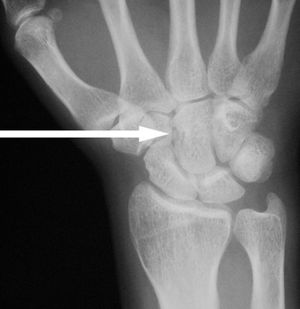

Capitate fracture

Imaging

- Plain films of hand

- Often overlooked due to accompanying scaphoid fracture or lunate/perilunate dislocation